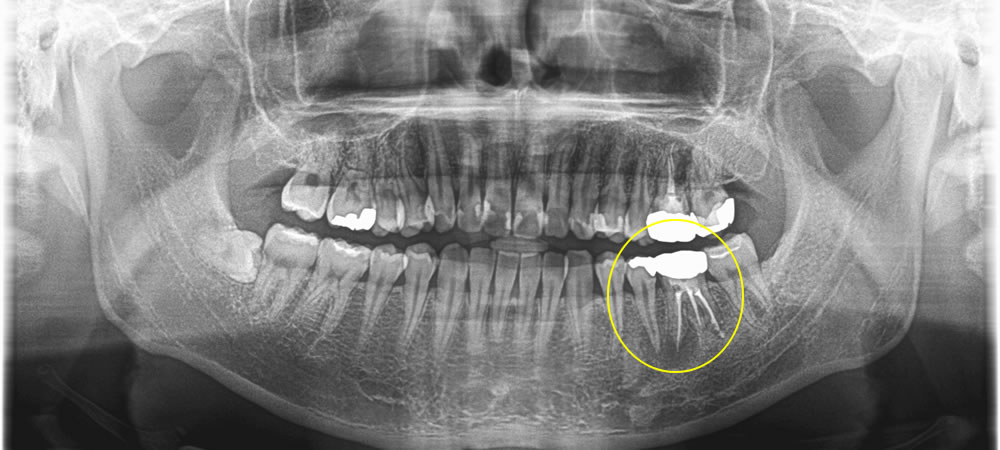

保存不可能な2本の歯を抜歯後にインプラントで治療した症例

こちらの患者さまは、左下の奥歯が噛むとジンジン痛いとのことで来院されました。

レントゲンでの検査の結果、昔他院で神経の処置をした歯の根っこに膿が溜まって炎症が起こっていることが痛みの原因であることがわかりました。

放置してしまった期間が長かったせいで手前の歯にも膿が溜まってしまっていたため、2本抜歯し、インプラントを埋入しました。膿が大きく、骨の欠損範囲も大きかったため、骨を増やすための骨造成も合わせて行いました。